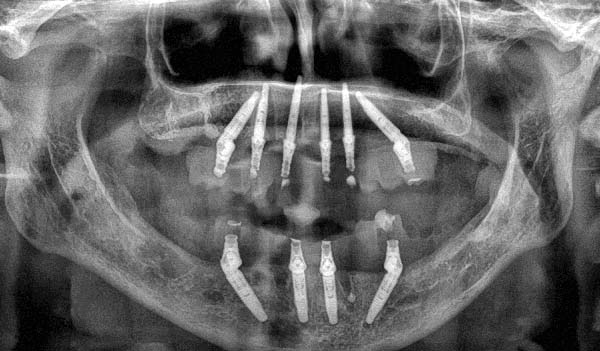

Wegen des sehr spongiösen Knochens wurden im Oberkiefer sechs Implantate geplant, um die Gesamtstabilität zu erhöhen, falls intraoperativ die gewünschten Eindrehwerte über 35 N/cm nicht erreichbar wären.